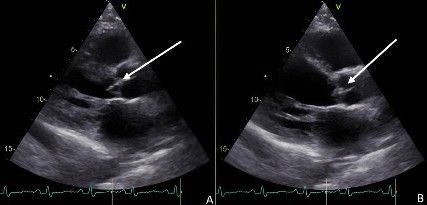

Posteriormente se le realizó un segundo hemocultivo, indicando bacteriemia persistente; se ejecutó un examen de sangre oculta en heces con el propósito de descartar cáncer de colon, no obstante, su resultado fue negativo. Se realizaron estudios de serología para VIH y antígeno de superficie de hepatitis B (Tabla 2) para descartar inmunodeficiencia, cuyos resultados fueron negativos. Adicionalmente, se realizó un ecocardiograma transtorácico (Eco TT), en el cual se evidenció vegetación en la válvula aórtica de 1,4 cm x 0,4 cm, estenosis de la válvula mitral secundaria a esclerosis de la válvula, la cual concuerda con la edad del paciente, y cardiopatía dilatada de origen valvular (Figura 2). Asimismo, como estudio prequirúrgico se solicitó una angiografía por tomografía computarizada de coronarias; sin embargo, pese a las dosis de betabloqueador y por no existir un control cronotrópico negativo, no se logró realizar, por lo que se llevó a arteriografía coronaria con cateterismo derecho e izquierdo, dando como único hallazgo positivo hipertensión pulmonar moderada.

Figura 2 Ecocardiograma transtorácico con presencia de vegetación en válvula aórtica nativa. A) y B) Válvula aortica cerrada.

Entre las estrategias diagnósticas para esta patología están los hemocultivos, los cuales constituyen un factor clave, ya que permiten diagnosticar del 96 % al 98 % de las bacteriemias 13. En el presente reporte, si bien se tomaron hemocultivos, el retraso en la comunicación entre la institución prestadora de servicios de salud y la falta de un tratamiento oportuno generaron el progreso de la patología hasta el punto de provocar daño valvular. Otro de los métodos diagnósticos complementarios de la endocarditis bacteriana es el ecocardiograma. Dahl et al. realizaron uno de los primeros estudios en los que se usa sistemáticamente esta imagen diagnóstica en pacientes con bacteriemia por E. faecalis con el fin de diagnosticar endocarditis bacteriana. Plantean la existencia del riesgo de realizar subdiagnósticos de endocarditis como consecuencia de la no realización de ecocardiograma al enfrentarse a casos de bacteriemias 5. En el caso descrito, podemos evidenciar que se le hizo un correcto diagnóstico de endocarditis bacteriana al ampliar el estudio de la bacteriemia solicitando el ecocardiograma transtorácico que mostró las vegetaciones.